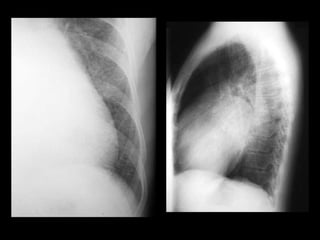

Trama broncovascular normal. Más intensa en las bases.

Trama broncovascular normal.Más intensa en las bases.